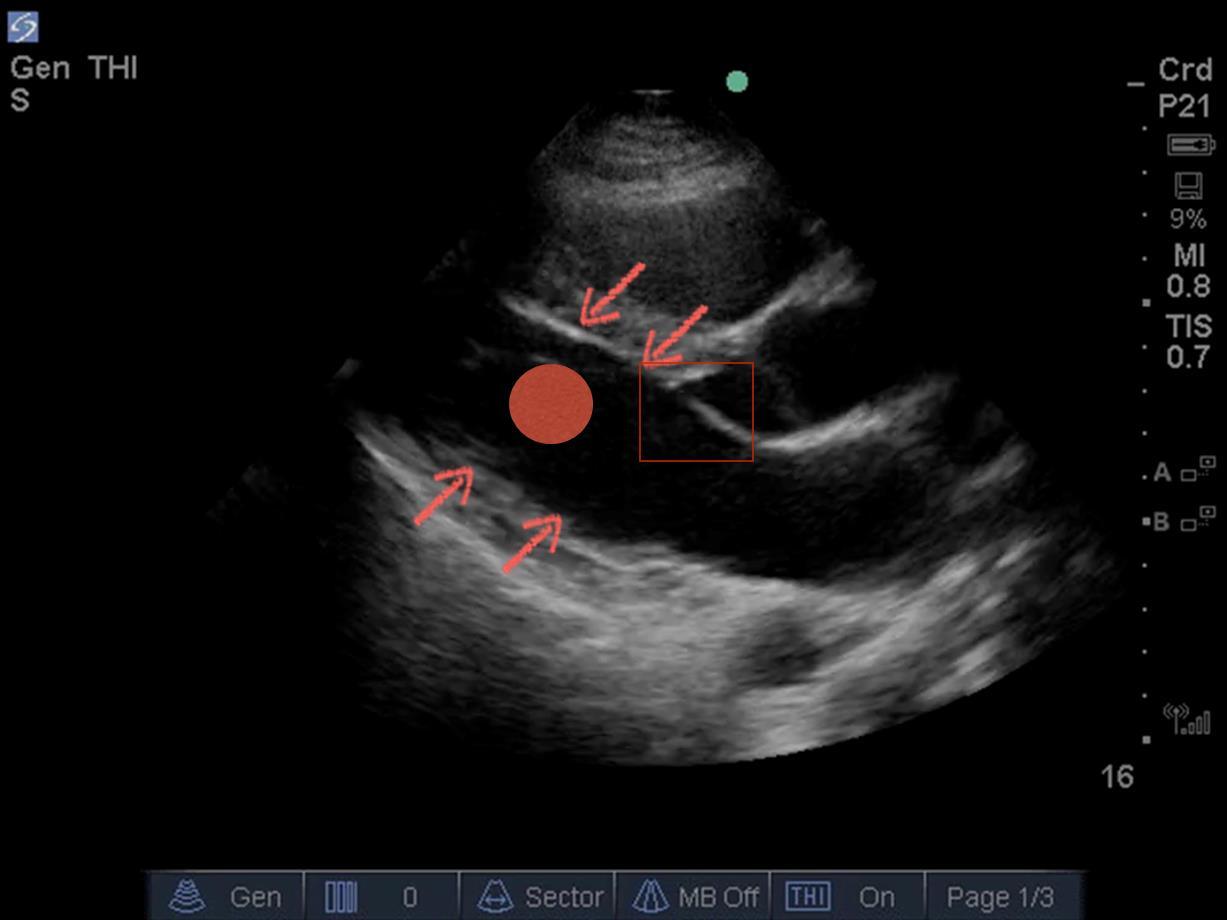

Engrosamiento del miocardio, desplazamiento endocárdico, STPE - Imagen

Flechas rojas: mire aquí para evaluar el engrosamiento del miocardio

Punto rojo: mire aquí para evaluar el desplazamiento del endocardio

Cuadro rojo: mire aquí para evaluar STPE